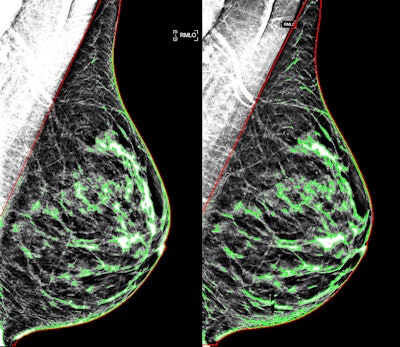

But the fact that more breast imagers are using synthesized 2D images with DBT to reduce radiation begs the following question: How well do the synthesized images estimate density, compared with their digital counterparts? Turns out they do just fine, wrote a team led by Dr. Emily Conant from the University of Pennsylvania in Philadelphia. The group evaluated the agreement between automated estimates of breast density from standard and synthesized mammograms (Radiology, January 25, 2017).

"Fully automated estimates of breast density made from synthetic mammograms are ... comparable to those made from standard-dose mammograms," the group wrote. "This may be important, as standard two-dimensional mammographic images are increasingly being replaced by synthetic mammograms in DBT screening."

For the study, the researchers included 3,668 negative DBT screening exams that had been performed over a four-month period; both standard-dose and synthesized mammograms were available for each exam. They then assessed agreement between density estimates derived from each type of mammogram using automated software developed at the university.

Automated measures of breast density from synthesized mammographic images compared well with those from standard mammograms, with a correlation coefficient of r = 0.92 (p < 0.001), the group found.